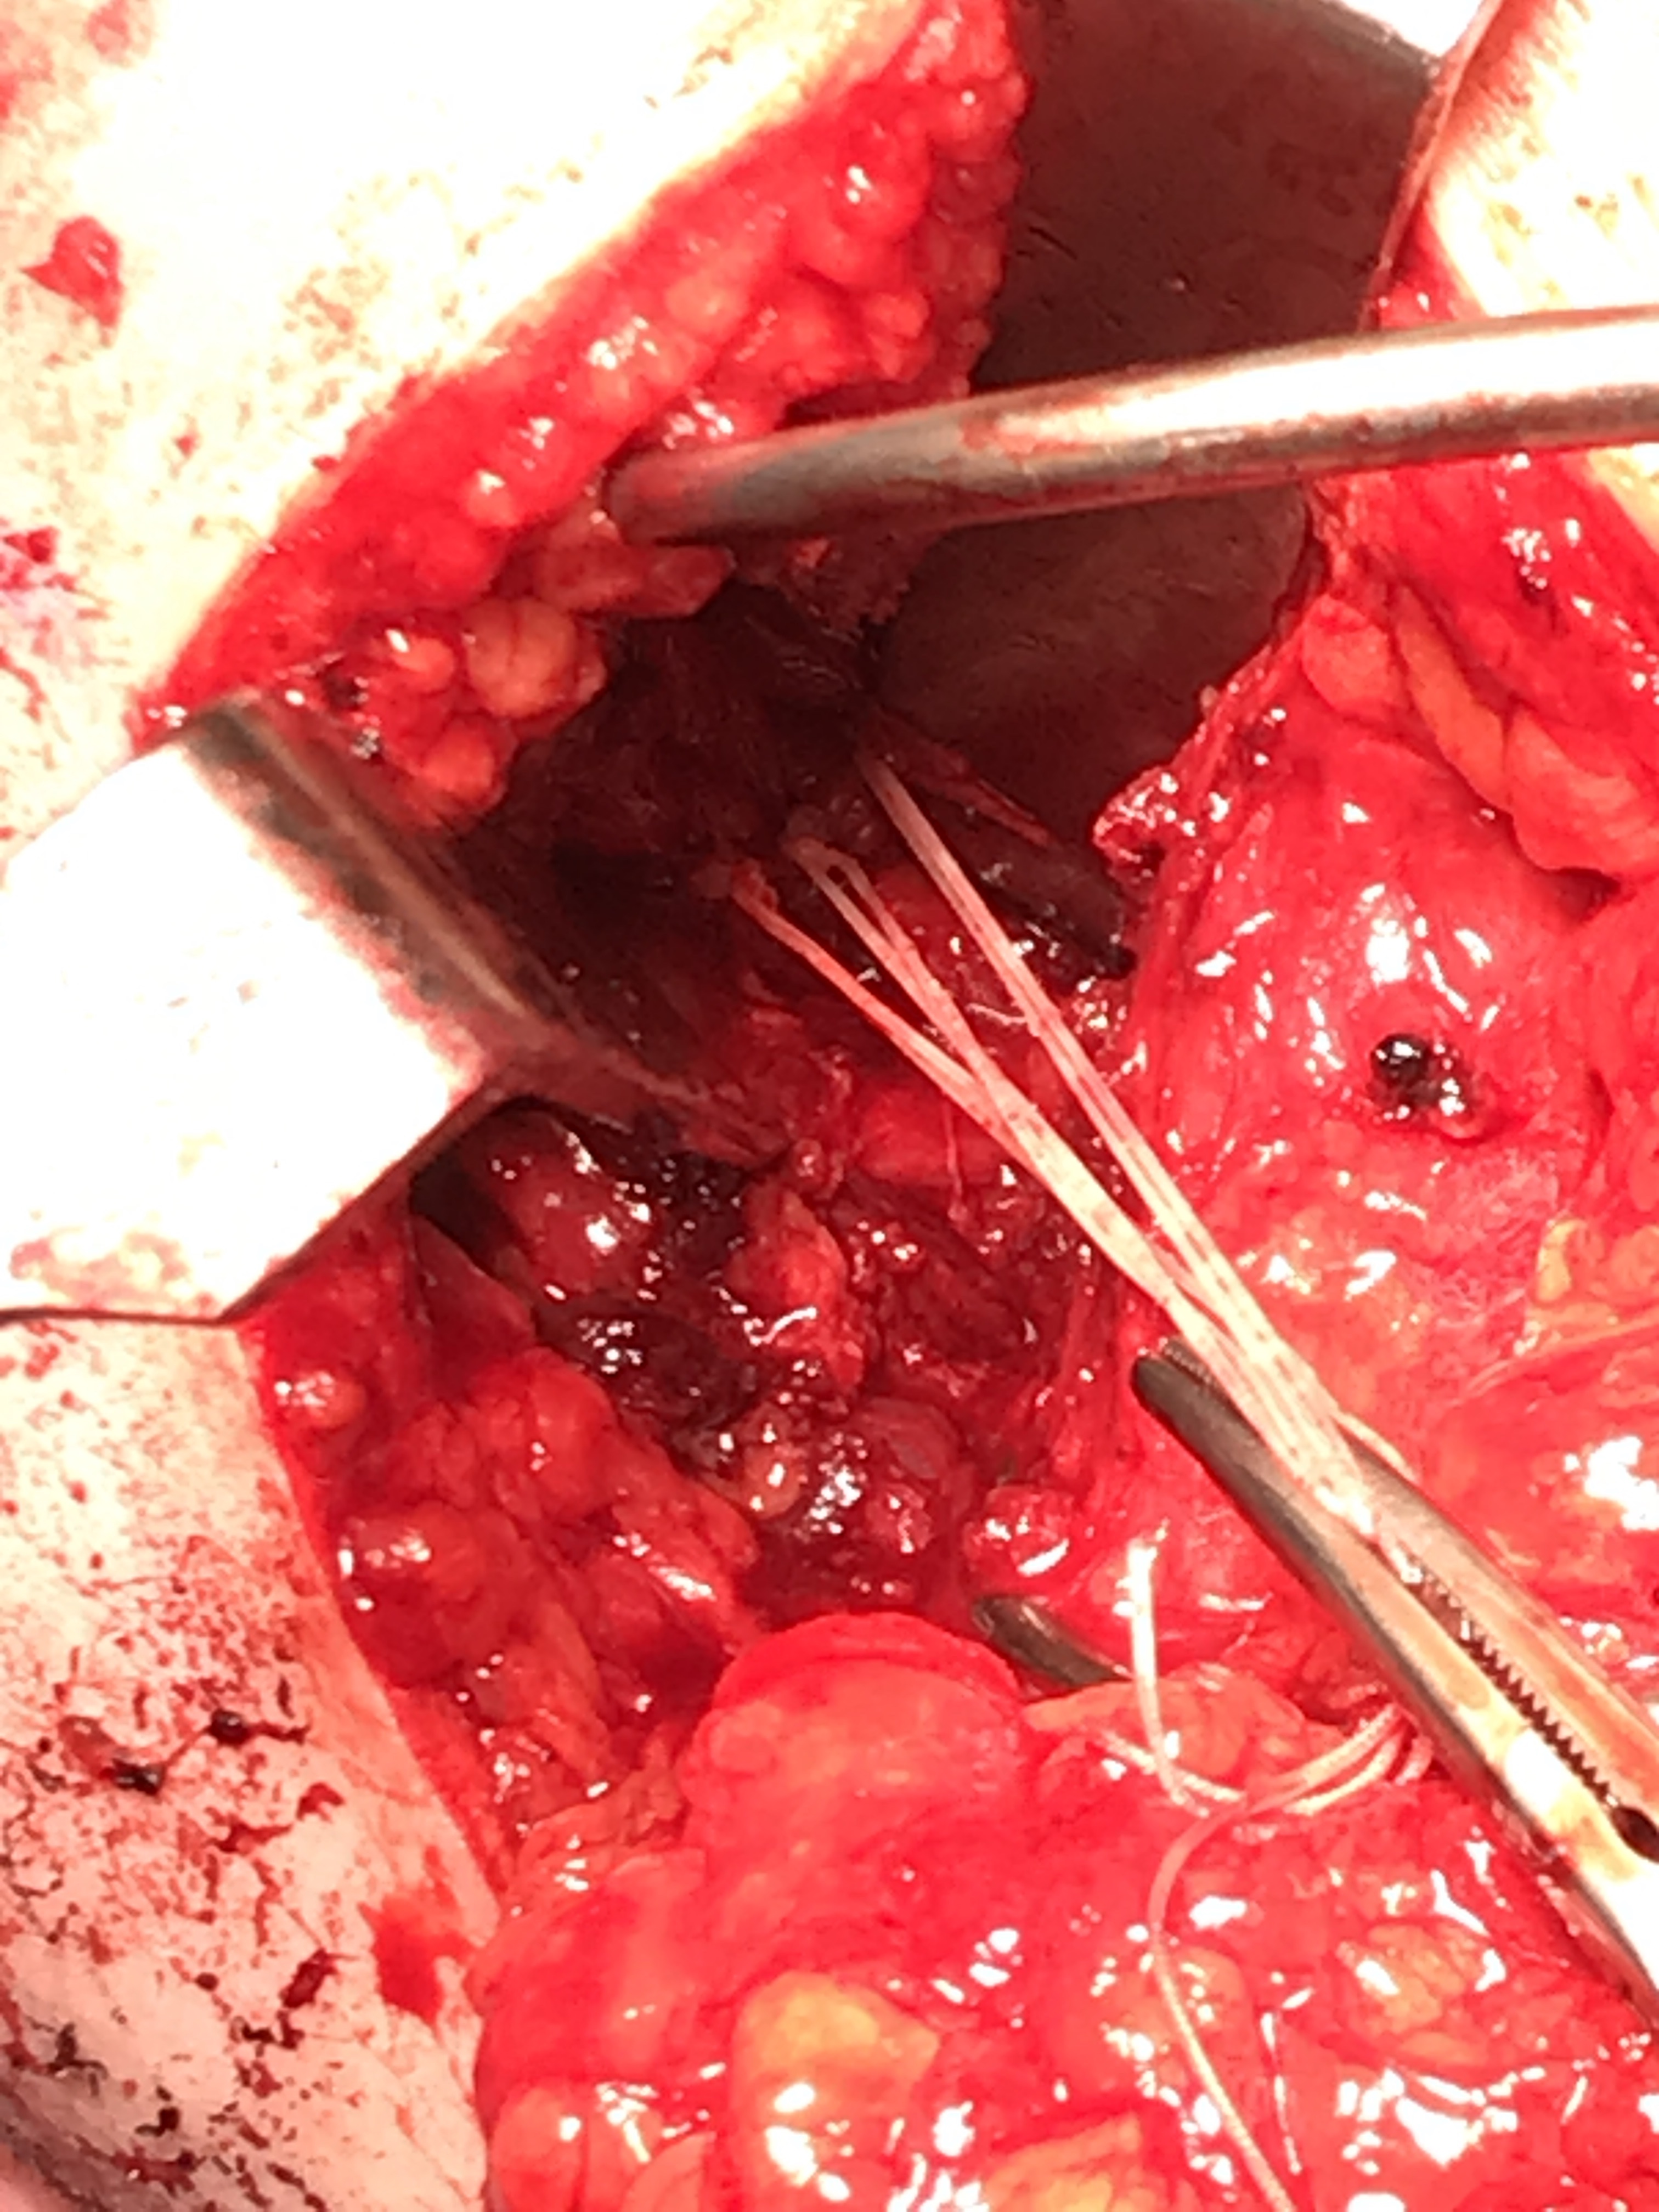

Posterior glenoid reconstruction / bone block procedure

Technique

Beach chair or lateral position

- posterior approach / L shaped incision

- elevate or detach deltoid from scapular spine

- detach infraspinatus

- iliac crest or distal tibial allograft

Identify and elevate deltoid / detach from scapular spine / identify infraspinatus

Identify interval between infraspinatus and teres minor, detach and reflect infraspinatus to expose posterior capsule and glenoid